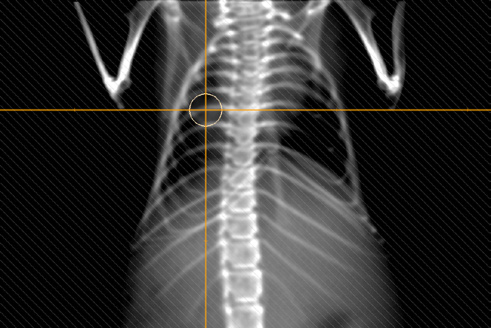

Figure 1. A 3D rendering of a segmented whole-body mouse image, including the geometry of a circular cone beam.

Two irradiation techniques are supported in μ-RayStation: 3D-CRT and static arc. 3D-CRT plans comprise of one or more beams with fixed angles and collimation for each beam (visualization of a beam can be seen in Figure 1. An example of a 3D-CRT treatment plan dose is displayed in Figure 4). Static arc plans comprise of one or more arc beams with fixed collimation and user specified start and stop gantry angles.

Figure 7. A digitally reconstructed radiograph for one of the beams on Figure 4.